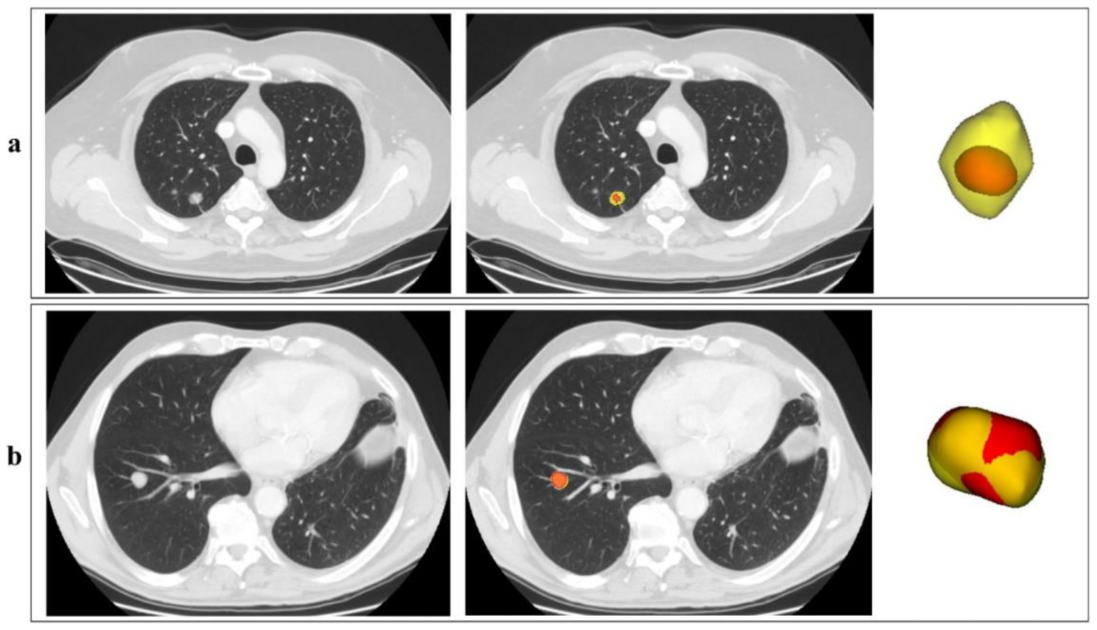

3.1. Manual and Automatic Segmentation